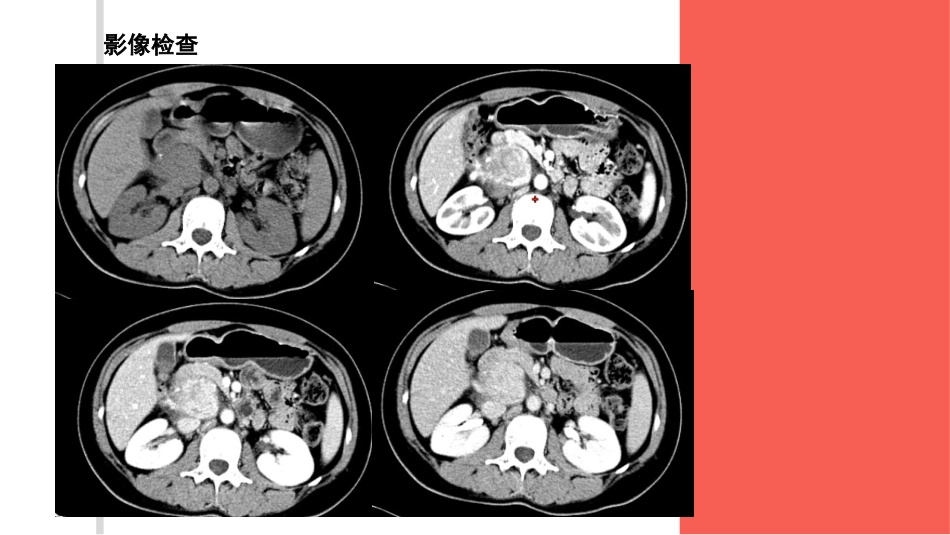

巨淋巴结增生(Castleman病)读片王洁2016-7-18病史•女,29岁;体检B超发现腹膜后占位一周余。患者一周前体检B超发现腹膜后占位,无明显不适,无血压升高。•体格检查及实验室检查未见明确异常。影像检查病理结果•巨淋巴结增生(Castleman病)巨淋巴结增生(Castleman病)少见的良性淋巴组织增生性病变;胸部多见,腹盆部少见局限型:多局限于单个淋巴结发病,约90%为透明血管型弥漫型:全身多发淋巴结增大,多数为浆细胞型•单发类圆形、椭圆形软组织肿块影,伴或不伴卫星结节(淋巴结肿大)•边界多较清晰,密度多均匀,病灶极少伴有出血、坏死,30%病例可伴有分支状或斑点状钙化,部分病灶周围筋膜增厚•CT增强扫描:动脉期明显强化,门静脉期及延迟期仍持续强化,强化方式与大血管相似;均匀或不均匀强化当肿块直径>5cm时,可为不均匀强化,表现为增强早期肿块内有星状或裂隙状不强化区,延迟扫描不强化区范围可缩小或消失当肿块直径<5cm时,病灶多为均匀强化;部分病灶周边及内部可见增粗、迂曲的供血血管,增强早期病灶周边呈“镶边状(rim-like)”强化鑒別診斷•嗜鉻細胞瘤•神經源性腫瘤異位嗜鉻細胞瘤•異位位于腹膜后、纵隔、肝门和膀胱圆形或类圆形软组织肿块,边缘清楚;密度可均匀或不均匀,可有钙化、出血,囊变;多发大小不-,恶性大、外形不规则且常侵犯邻近结构或出现转移•增强:强化明显;不均匀神經源性腫瘤•多位于脊柱旁、肾脏内侧和盆腔骶前区等神经组织丰富的部位肿块呈卵圆形或梭形、边缘清晰•密度多不均匀,瘤内可含有脂类成分;多数实质性肿瘤或囊实性肿瘤的实质部分密度较低(低于肌肉),少部分肿瘤高于肌肉,与肌肉等密度的肿瘤相对少见,瘤体大者可见坏死、囊变区,偶见钙化灶•增强扫描病灶轻度或明显强化,但强化不均匀,发生囊变时呈环形强化,坏死、囊变区无强化